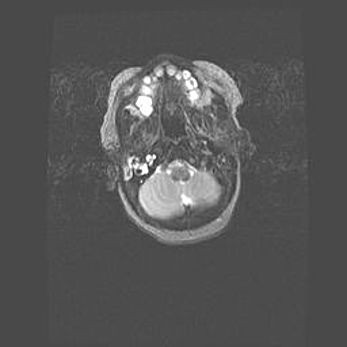

Церебральная ишемия II.

Возраст: 5 дней

Вес: 3400 г

Пол: женский

Окружность головы: 35 см

Срок гестации: 39 недель

Церебральная ишемия – это заболевание, характеризующееся недостаточностью (гипоксией) либо полным прекращением (аноксией) снабжения мозга кислородом по причине закупорки одного или нескольких сосудов. Это приводит к  что метаболическим расстройствам различной степени тяжести в тканях головного мозга, развитию коагуляционных некрозов и гибели нейронов.